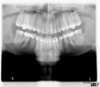

Panoramique